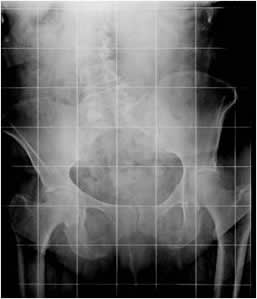

La dismetría de los miembros inferiores generalmente ocurre por acortamiento, que desencadena mecanismos compensatorios. Es común el acortamiento de pocos milímetros sin repercusión clínica y con predominio en el lado derecho. Entre 5 y 20 mm de diferencia, hay basculación de la pelvis. Mas de 20 mm ocasiona escoliosis vertebral y deformidad en rodillas y tobillos. (3). (Fig 100 y 101).

Fig 100. Desbalance pélvico.

Rx AP. Acortamiento izquierdo, con elevación de la cresta iliaca derecha. (Línea continua).

Fig 101. Desbalance pélvico.

Rx AP. Acortamiento derecho, con elevación de la cresta iliaca izquierda y escoliosis lumbar derecha.

El desbalance pélvico se determina mediante la distancia entre líneas horizontales, que pasan sobre el borde superior de las crestas iliacas. (3). (Fig 106).

Fig 106. Acortamiento.

Rx AP. Acortamiento del fémur izquierdo, como secuela de fractura consolidada en varo. Se encuentra desbalance pélvico, con elevación de la cresta iliaca derecha.